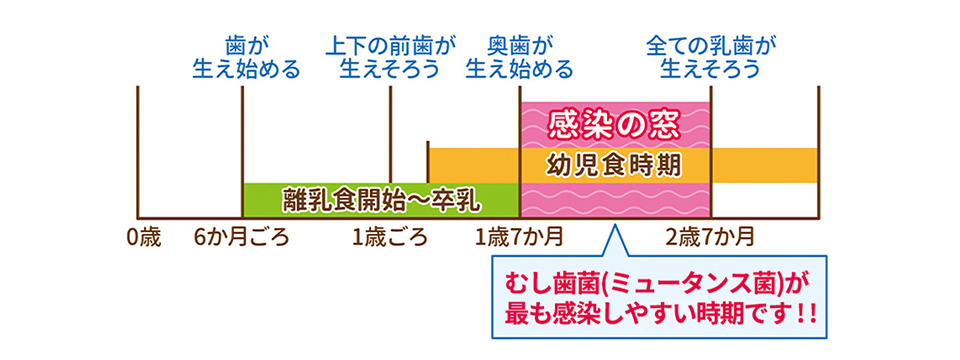

当院では一番最初に歯が生え始める(下の前歯)生後6か月頃からを推奨しております。

早い時期から予防処置を行うことで予防効果も高くなります。また、早い時期に歯医者へ通い始めることで歯医者さんに対する抵抗感も少なく慣れていくことができます。

お子さんの定期検診は3ヶ月に1回のペースを推奨しております。お子さんのむし歯は歯と歯の間からできているため、穴が空いてきた時には大きくなっていることがほとんどです。

そのような状況を防ぐためにも3か月に1回の検診が重要となります。